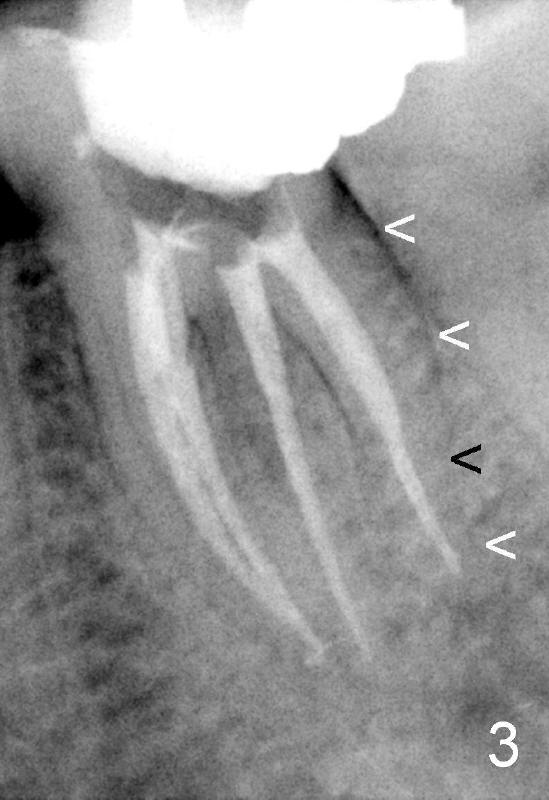

其实本文题目是如何让植牙病人找上门。冯女士四十二岁,四五年前因左下六牙痛第一次登门就诊,X光片显示牙根很长(图一),近中根根尖有阴影(>),那根牙根弯曲,总之,稀里糊涂开始根管治疗,结果有四根根管(图二),又长又弯,远中舌侧根断针(>),但是重新通过,辛辛苦苦完成根管治疗时才发现远中舌侧根弯弯曲曲(图三箭头,黑色箭头指向原来断针)。这些年来这颗牙齿没问题,但是左上七号牙老是发炎,全景片表明那颗牙齿根分叉处有阴影(图四箭头),一直劝她拔牙,植牙,上个月她终于同意拔牙,准备年底植牙。只有认认真真为病人解决痛苦,才能赢得他们信任,一旦他们需要进一步治疗,也会乐意开口。根管治疗做起来吃力,但是最能显示赤胆忠心。做好根管治疗是开展植牙第一步,愿意保留牙齿的人,视牙如金,如果我们尽力而保留不了,他们还是愿意更上一层楼;轻易拔牙的病人很少后来回来做植牙。